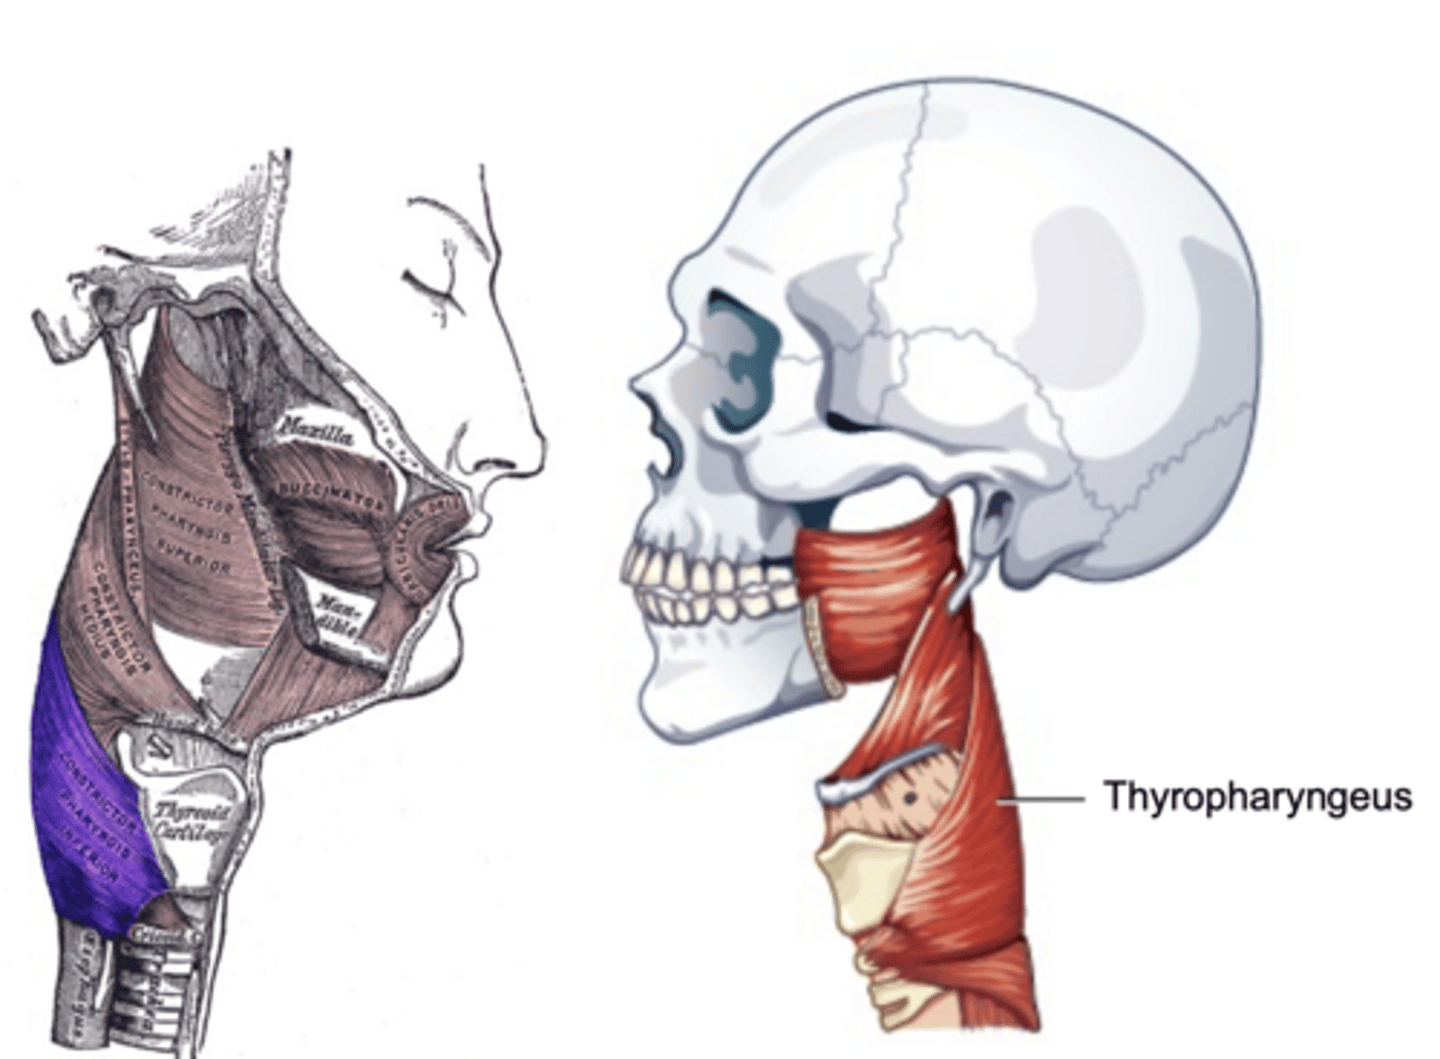

Thyropharyngeus Figure

Inferior Constrictor -

Thyropharyngeus Description

Inferior Constrictor consists of the

Thyropharyngeus and the Cricopharyngeus

Inferior Constrictor is thickest and strongest of constrictor muscles

Thyropharyngeus is the majority of the Inferior Constrictor

Origin -thyroid cartilage

Course - fans out posteriorly and medially

Insertion - midline raphe

Action - reduce diameter pharynx